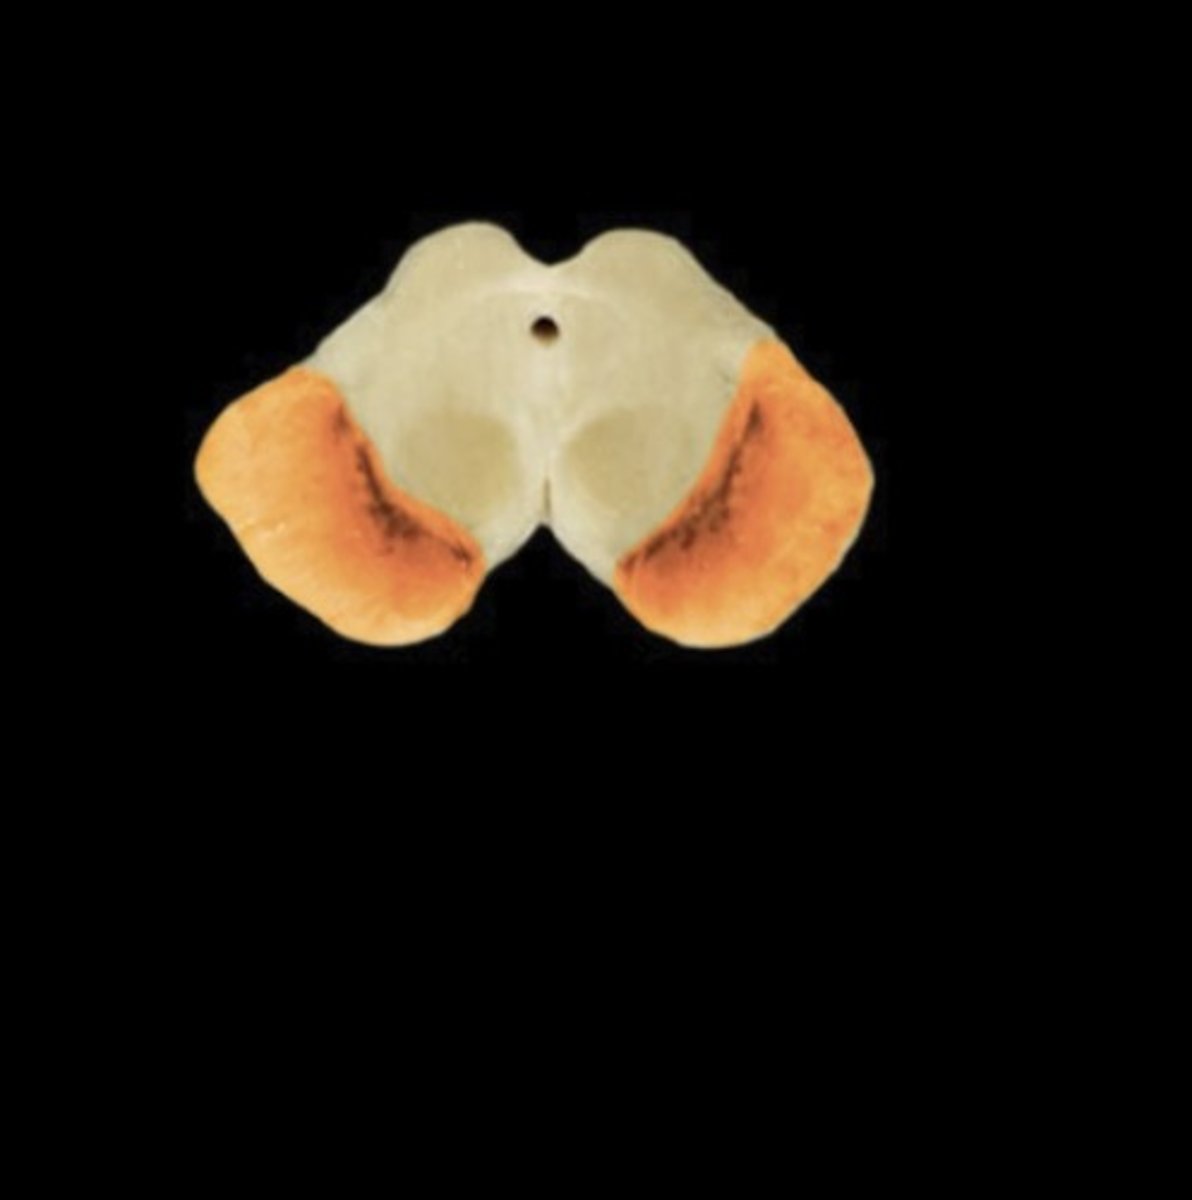

Substantia Nigra

Name this structure

Cerebral aqueduct

Name this structure

Cerebral crus

Name this structure

Cerebral Peduncle

Name this structure

Corticospinal tract

Name this structure